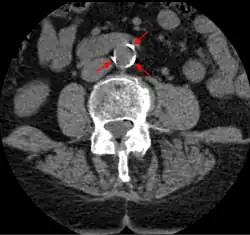

The calcification deposits,[74] after they have become sufficiently advanced, are partially visible on coronary artery computed tomography or electron beam tomography (EBT) as rings of increased radiographic density, forming halos around the outer edges of the atheromatous plaques, within the artery wall. On CT, >130 units on the Hounsfield scale (some argue for 90 units) has been the radiographic density usually accepted as clearly representing tissue calcification within arteries. These deposits demonstrate unequivocal evidence of the disease, relatively advanced, even though the lumen of the artery is often still normal by angiography.

Examples of anatomical detection methods include coronary calcium scoring by CT, carotid IMT (intimal media thickness) measurement by ultrasound, and intravascular imaging techniques, such as intravascular ultrasound (IVUS), and intravascular optical coherence tomography (OCT),[85][86] allowing direct visualization of atherosclerotic plaques.